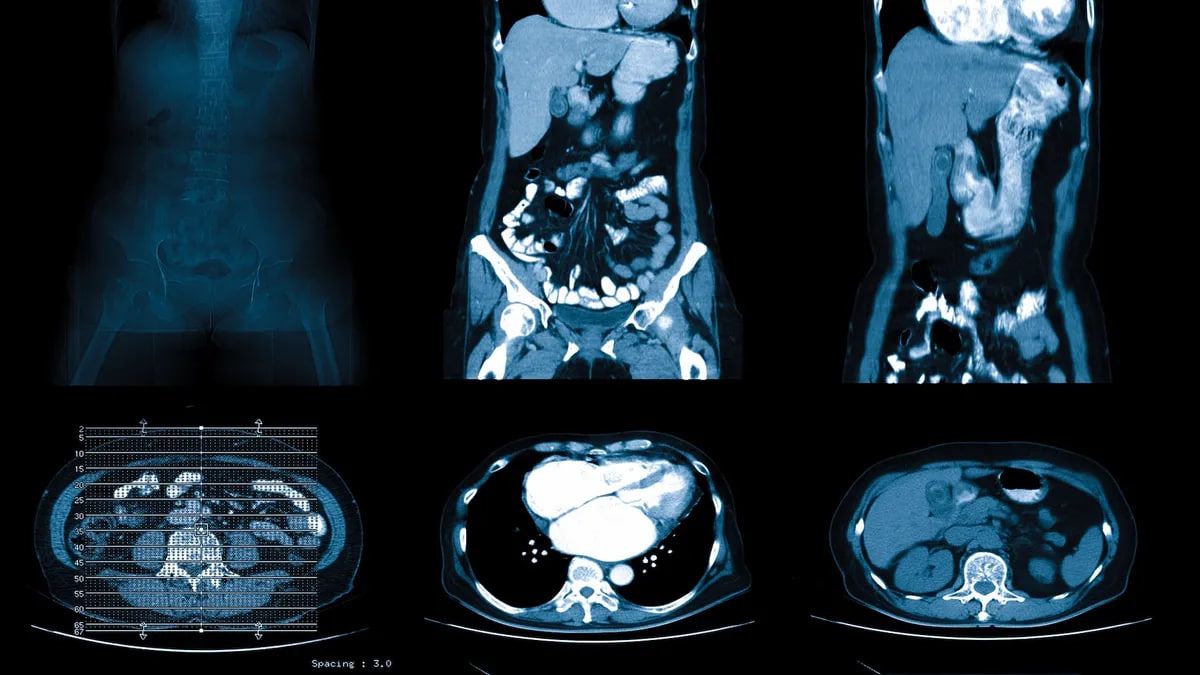

Врачам удалось спасти жизнь девочке после того, как у нее развилось редкое и потенциально опасное для жизни состояние, называемое заворотом желудка, при котором часть или весь желудок возвращается более чем на 180 градусов. Когда это случилось с 12-летней девочкой, она испытывала ужасные боли, не могла нормально дышать и не могла опорожняться.

Согласно сообщению, девочка выжила благодаря своевременной диагностике и хирургическому лечению. Однако примерно в 30–50% случаев это заболевание приводит к смерти.

Заворот желудка обычно вызывается грыжей, при которой часть желудка выпячивается в грудную полость через отверстие диафрагмы. Однако в случае с девочкой живот свернулся сам собой, потому что удерживающие ее на месте связки были ослаблены.